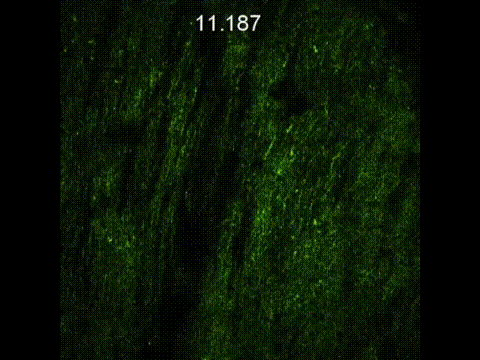

Neuroscience

Through high-speed image capturing JadeBio can directly conduct the in vivo mouse brain imaging. Also, through long-term observation, the real-time physiological signal changes in the mouse brain can be analyzed and considered the most direct proof of the true physiological response.